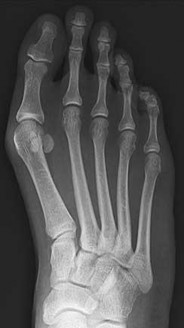

Figures 9a and 9b are the radiographs of a 19-year-old woman with a painful juvenile bunion. The pathologic findings associated with this deformity

include a

The radiographs show a hallux valgus deformity with a laterally deviated distal metatarsal articular surface, a large intermetatarsal angle with medial deviation at the first metatarsocuneiform joint, an elongated medial collateral ligament, and a contracted lateral collateral ligament. There is no distal 1-2 transverse intermetatarsal ligament. The distal transverse ligament in the first interspace extends from the second metatarsal to the lateral (fibular) sesamoid, remains intact, and keeps the sesamoids in a lateral position as the first metatarsal head migrates medially.